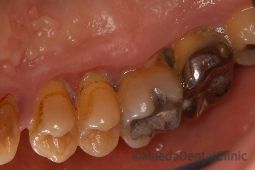

重度歯周炎

重度の歯周炎歯槽骨の吸収が進み、歯の周りの骨がほとんどなくなり、歯周ポケットは8mm以上になります。ここまで進行すると、歯肉から自然に出血し,膿が出ることもあります。歯のぐらつきがひどく、噛むと痛みが出てきます